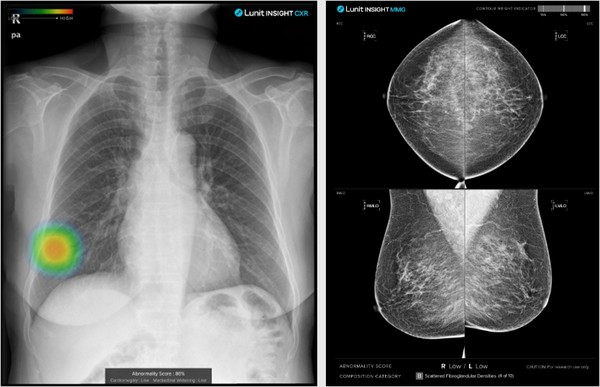

- 루닛 스코프(Lunit SCOPE)는 AI 기반의 바이오마커 분석 플랫폼으로, 암 환자의 조직 슬라이드를 분석하여 면역항암제에 대한 반응을 예측하는 도구입니다.

- 이를 통해 의료진은 환자에게 맞춤형 치료를 제공할 수 있으며, 제약사들은 신약 개발 과정에서 임상 시험을 최적화할 수 있습니다.

- 루닛 스코프는 종양의 미세 환경을 분석하여 치료 반응성을 예측하는 데 중요한 역할을 합니다.